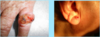

A: Describe Histology (3)

B: Dz

A: image

B: [Squamous Cell Carcinoma]

A: Describe Histology in each image

B: Dz

A: image

B: [Squamous Cell Carcinoma]